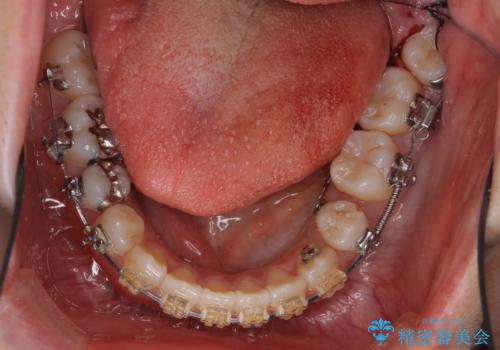

- 矯正装置

- 審美装置

下の小臼歯を抜歯しましたが、その代わり下の親知らずを残して咬ませたので、歯の数は変わっていません。

ただし、左下の親知らずを残すには厚みのある歯ぐきを処置しています。(ディスタルウェッジ)